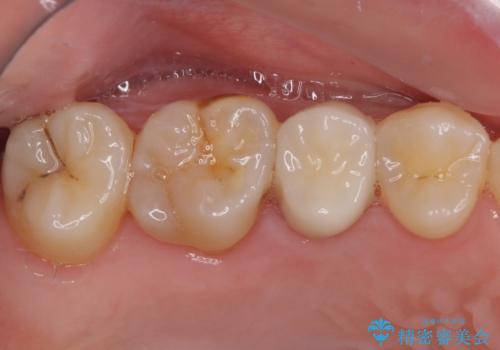

【根管治療】噛んだ時にしみる。最近になってズキズキ痛み、長引く痛みがある

担当医 河口智英